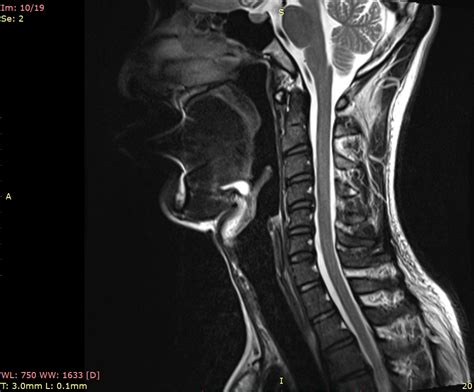

Left Side Swollen Lymph Neck